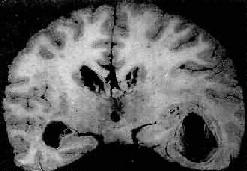

肉眼观,脑脊膜血管高度扩张充血,病变严重的区域,蛛网膜下腔充满灰黄色脓性渗出物,覆盖着脑沟脑回,以致结构模糊不清(图16-10),边缘病变较轻的区域,可见脓性渗出物沿血管分布。在渗出物较少的区域,软脑膜往往略带混浊。脓性渗出物可累及大脑凸面矢状窦附近或脑底部视神经交叉及邻近各池。由于炎性渗出物的阻塞,使脑脊液循环发生障碍,可引起不同程度的脑室扩张。

图16-10 化脓性脑膜炎

蛛网膜下腔内有多量脓液堆积以致大部分脑表面的沟回结构不清;脑膜血管高度扩张充血